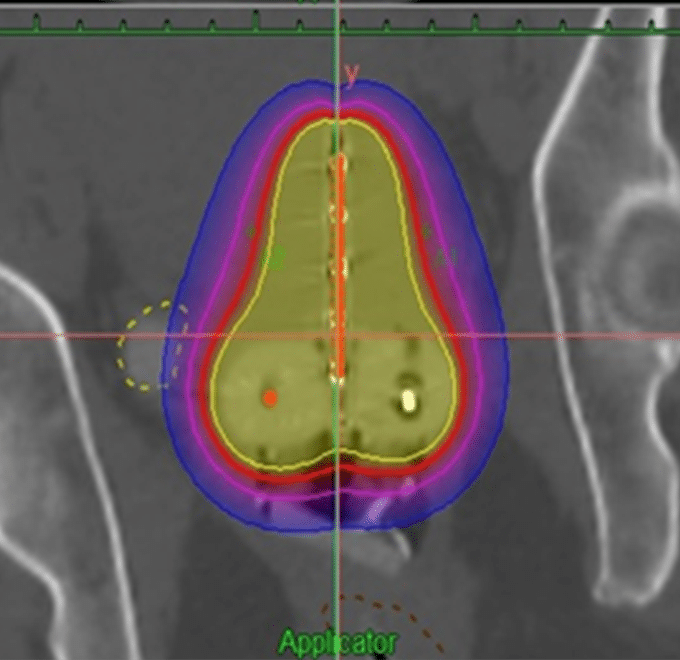

Braquiterapia

A diferencia de los otros tipos de radioterapia, la braquiterapia es una forma de radiación interna, generalmente utilizada para lesiones reducidas. Se coloca material radioactivo en la zona del tumor o en donde se extirpó un tumor para esterilizar el área. Dependiendo de la dosis, la ubicación en el cuerpo, el tipo de cáncer, entre otras cosas, la fuente de radiación puede permanecer unos minutos, varios días o indefinidamente. Puesto que el cuerpo emite radiación por algún tiempo, se le indicarán medidas de seguridad a seguir. En nuestro centro contamos con braquiterapia de alta tasa Iridio 192 ambulatorio y técnica 3D con menor morbilidad.

Radiografía de braquiterapia.